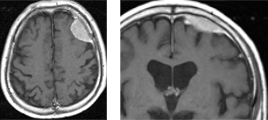

円蓋部髄膜腫

脳の表面を覆う硬膜から発生するタイプで最も頻度の高い腫瘍です。相当な大きさにならないと症状をきたしにくいことが多いので、MRI検査で偶然に発見されることが多いです。

この症例は、当初軽度の頭痛を主訴にMRIを行なったところ左前頭葉に2cmほどの腫瘍が偶然発見されました(左)。ほとんど症状が無く、日常生活に支障がなかったため、1年に1度検査を行い、経過観察していましたが、3年後に4cmとなりました(右)。それでも頭痛は軽かったのですが、腫瘍のサイズが少しずつ大きくなってきたため本人も不安となり、相談の上、開頭手術を行なった症例です。

このように脳の表面にできた場合は、いきなり手術を決断しなくても、治療を受けるか否か検討する猶予はありますので、よく考えたほうが良いです。

(腫瘍のサイズが大きくなりすぎると手術もかなり難しくなることもあり、後遺症を残すことにつながりかねないので、そのタイミングを逃してはならないことは言うまでもありません。これについても当科では随時相談いたします。)